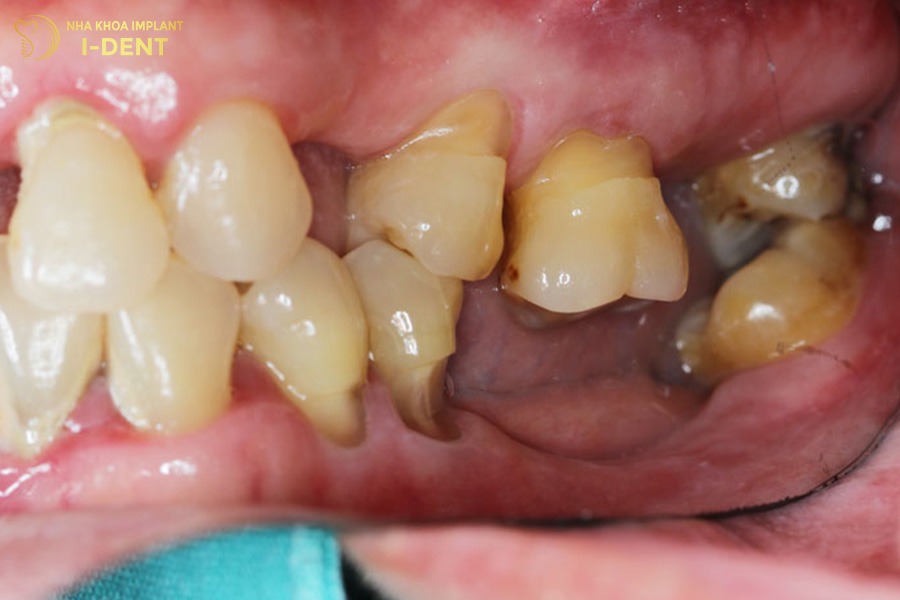

2.6. Răng lung lay, yếu và đau khi nhai

Răng trở nên lung lay hoặc yếu đi là một trong những dấu hiệu rõ ràng nhất của tiêu xương răng. Khi xương ổ răng bị tiêu, răng không còn điểm tựa vững chắc nên bị lung lay gây ra cảm giác đau âm ỉ và ê buốt khi ăn nhai.

Nguyên nhân chủ yếu thường xuất phát từ vệ sinh răng miệng kém khiến mảng bám và vi khuẩn tích tụ quanh chân răng gây viêm nha chu. Quá trình viêm này diễn ra âm thầm trong thời gian dài, phá hủy dần mô nâng đỡ và xương quanh răng. Khi mô xương không còn đủ để giữ răng thì bệnh nhân có thể cảm thấy đau, khó nhai hoặc mất răng hoàn toàn nếu không được điều trị kịp thời.

Răng lung lay, yếu và đau khi nhai.